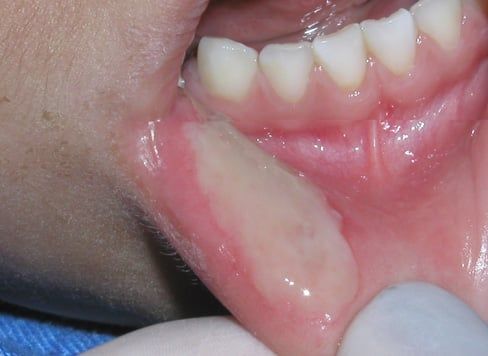

Ranula

This is a relatively uncommon benign cyst in children and adolescents that appears in the floor of the mouth as a result of blockage of the salivary duct located under the tongue. Just like other mucous retention cysts (formed by pooled saliva), Ranulas tend to be relatively painless; however most of them will require surgical treatment. Your dentist will refer you to an oral surgeon for evaluation and treatment.